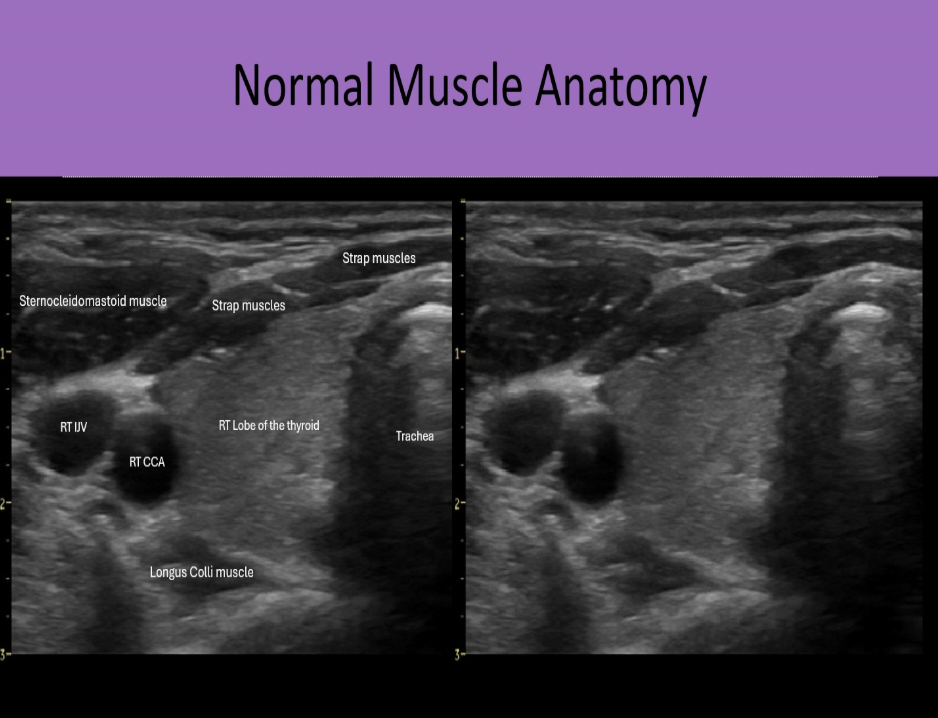

Which muscle group is located posterior to the thyroid gland?

C. longus colli muscle

Strap muscles are anteromedial to the gland. Sternocleidomastoid muscles are anterolateral to the gland. Longus Colli muscles are posterior to the thyroid lobes.

Find the sternocleidomastoid muscle

The sternocleidomastoid muscles are anterolateral to the thyroid gland

Which muscle group is located anterolateral to the lobes of the thyroid gland?

C. sternocleidomastoid

Which muscle group is located anteromedial to the lobes of the thyroid gland?

C. strap muscles

Find the longus colli muscle

The longus colli muscles are posterior to the thyroid gland